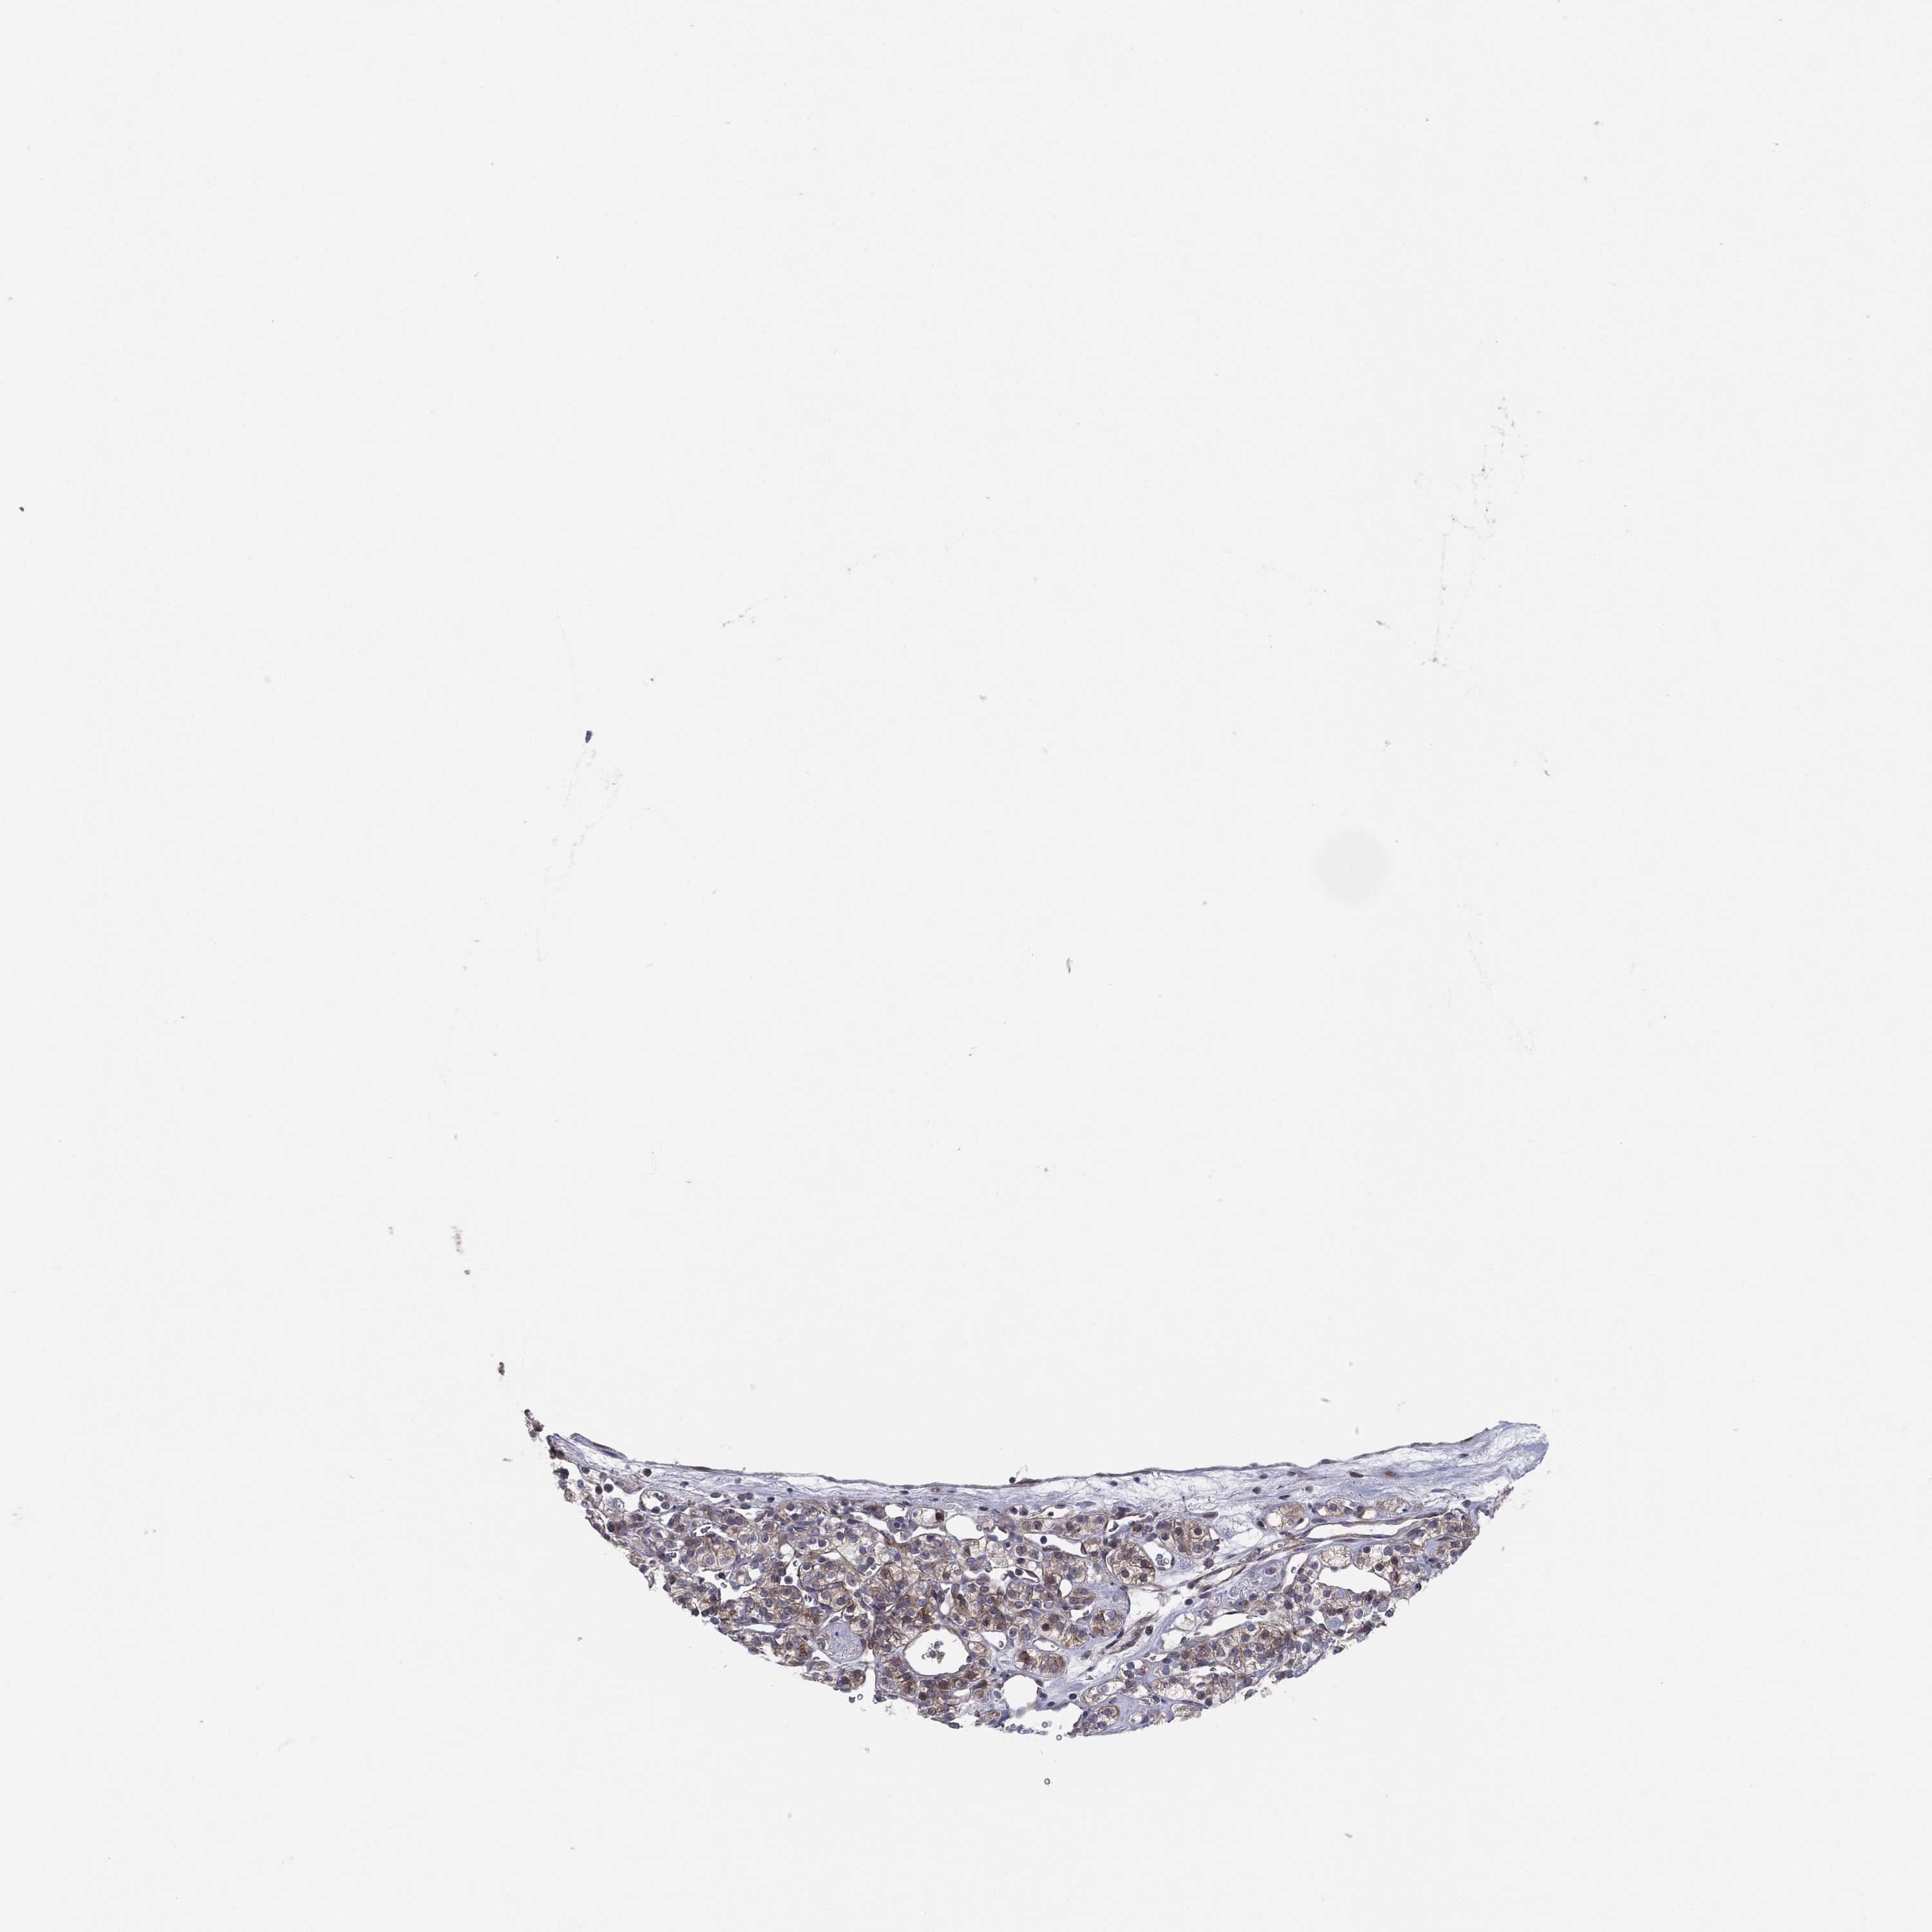

TCGA RNA samplesi

RNA-seq data is reported as average FPKM (number Fragments Per Kilobase of exon per Million reads), generated by the The Cancer Genome Atlas (TCGA) .

Normal distribution across the dataset is visualized with box plots, shown as median and 25th and 75th percentiles. Points are displayed as outliers if they are above or below 1.5 times the interquartile range. FPKM values of the individual samples are presented next to the box plot.

Average pTPM 12.7

Number of samples 100

UTP14A is not prognostic in Kidney Renal Clear Cell Carcinoma (validation)